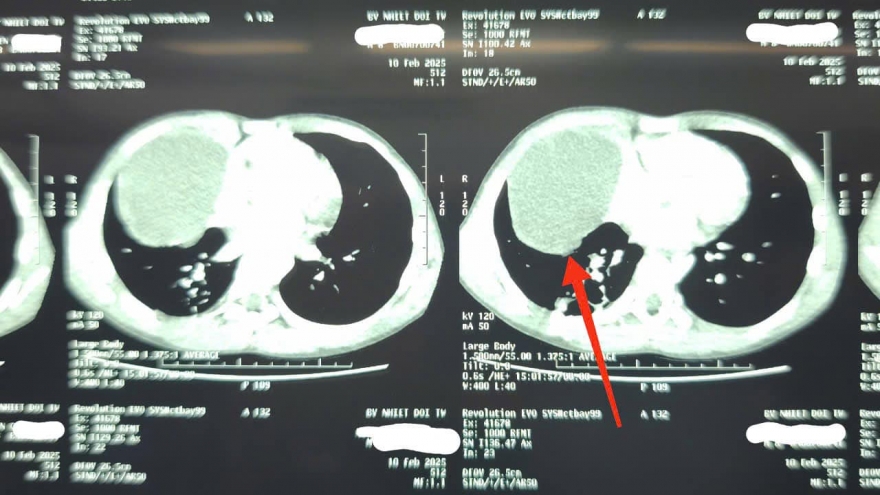

Mảnh xương vịt nằm trong phổi suốt 2 năm gây biến chứng nặng

VOV.VN - Các bác sĩ Bệnh viện Đa khoa Trung ương Cần Thơ vừa nội soi phế quản lấy thành công dị vật là mảnh xương vịt trong phổi người đàn ông gây biến chứng ho, đau ngực kéo dài, viêm phổi nặng.